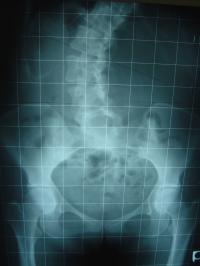

あなたが腰痛や足のしびれを訴えて医療機関に行き

レントゲンを撮影することでしょう。

この画像をみせられて、痛みの原因はズレやユガミ、

また骨のトゲや変形が神経を触っているからです。

椎間板がつぶれてしまい骨と骨がくっついてしまっている

からだと説得力のあるような説明で片付けられるかも

しれません。

しかし、この患者さんは腰痛・しびれ・膝の痛み、

肩こりなどの症状はなく普通に生活しています。

骨配列異常と痛みがリンクしていません。

ですからレントゲンを診せられても痛みの原因はよくわからず曖昧にされてしまいます。